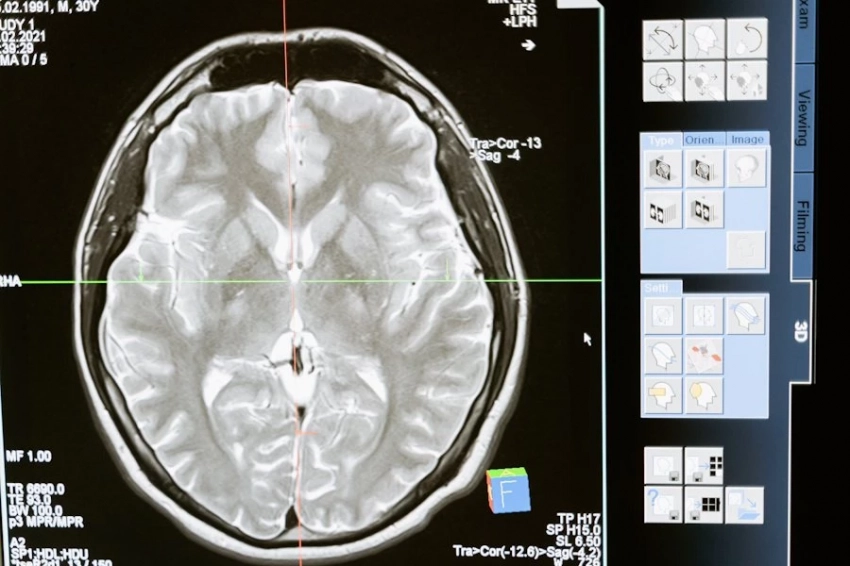

Американским исследователям удалось случайно зафиксировать активность человеческого мозга в момент смерти. Произошло это в процессе наблюдения за 87-летним пациентом с эпилепсией.

Ученые обратили внимание на любопытную деталь, какую ранее не фиксировали приборы. Исследователи записали мозговую активность за 15 минут до и после смерти.

Когда его сердце остановилось, приборы показали усиление гамма-волн, которые коррелируются с воспоминаниями и сновидениями. Всплеск длился в промежутке за 30 секунд до и после остановки сердца. Специалисты считают, что это свидетельствует: мозг воспроизводит яркие воспоминания в момент смерти.